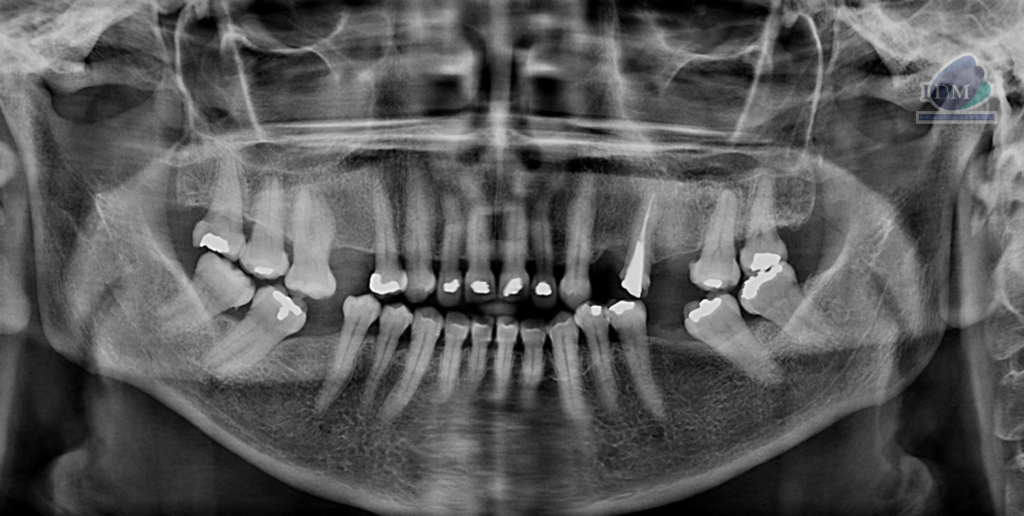

Paciente femenina de 56 años acude para evaluación de senos paranasales. A la evaluación de radiografía panorámica se observa aplanamiento del contorno condilar bilateral. La neumatización alveolar de ambos senos maxilares, múltiples restauraciones coronarias, placa cervical mineralizada y reabsorción ósea moderada del proceso alveolar.

Radiografia Panorámica